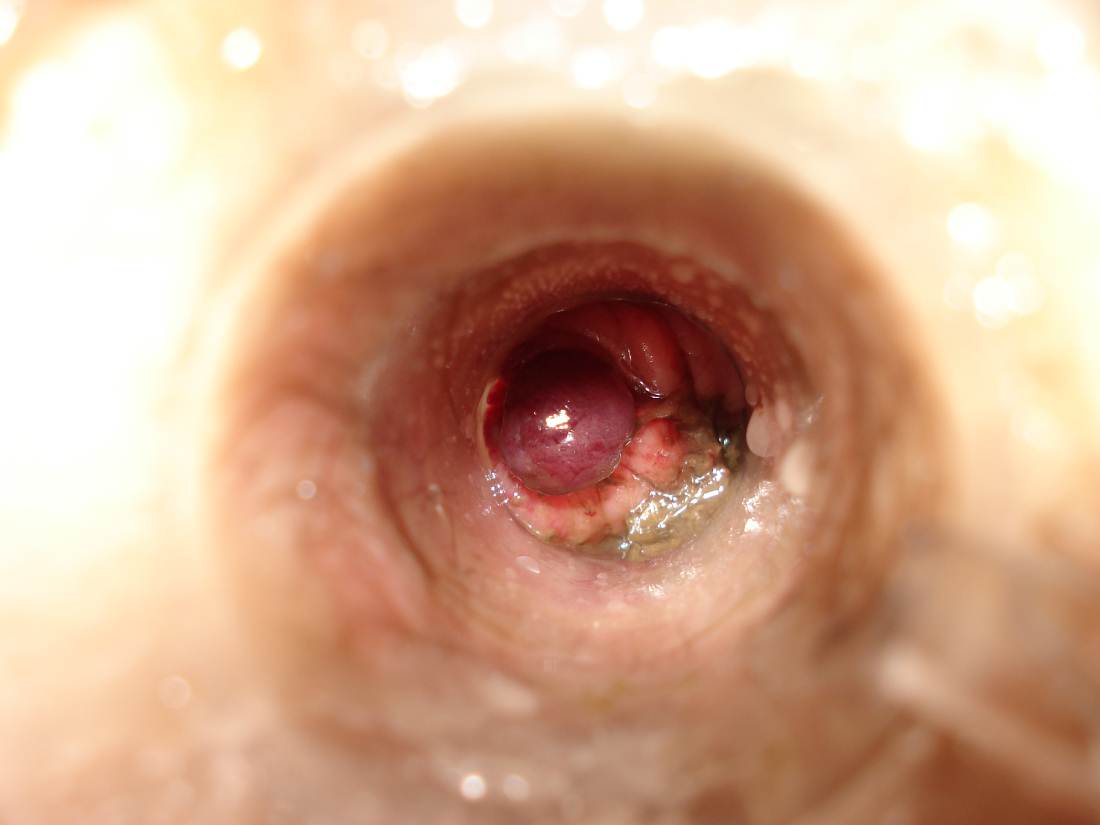

Внутренний геморрой у женщин

Полный размер 1100 × 825 пикселей Геморрой у женщин